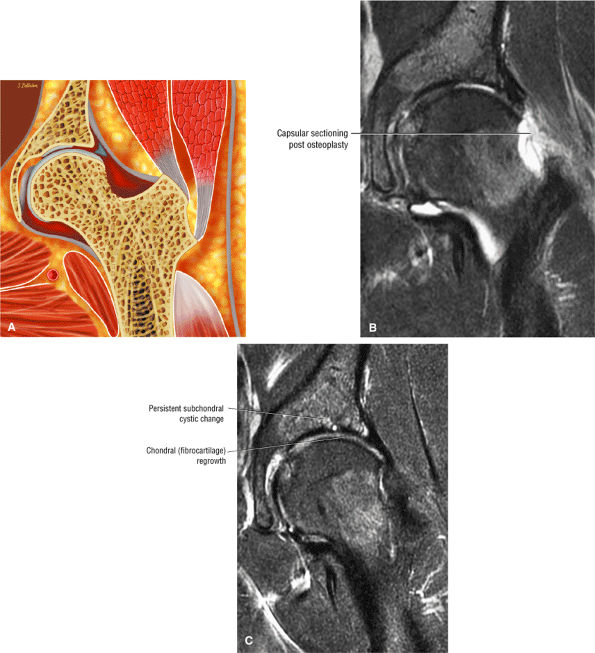

-

Fibrocystic change (Fig. 3.187) (herniation pits), which commonly occurs either anterior to the dysplastic bump (bump-cyst concordance) or anterior to the dysplastic bump (bump-cyst discordance) and is the result of flexion-induced pressure and not normal invagination of synovium210

Femoral cysts with fluid, synovial/fibrous, or fat signal intensity (Fig. 3.188), which may be associated with reactive subchondral edema (Fig. 3.189)

A femoral head chondral crease (Fig. 3.190) in DDH with labral hypertrophy. The femoral head articular crease is medial to the dysplastic bump. The bump and crease are characteristically proximal to the physeal scar, in comparison to non-DDH cam impingement.